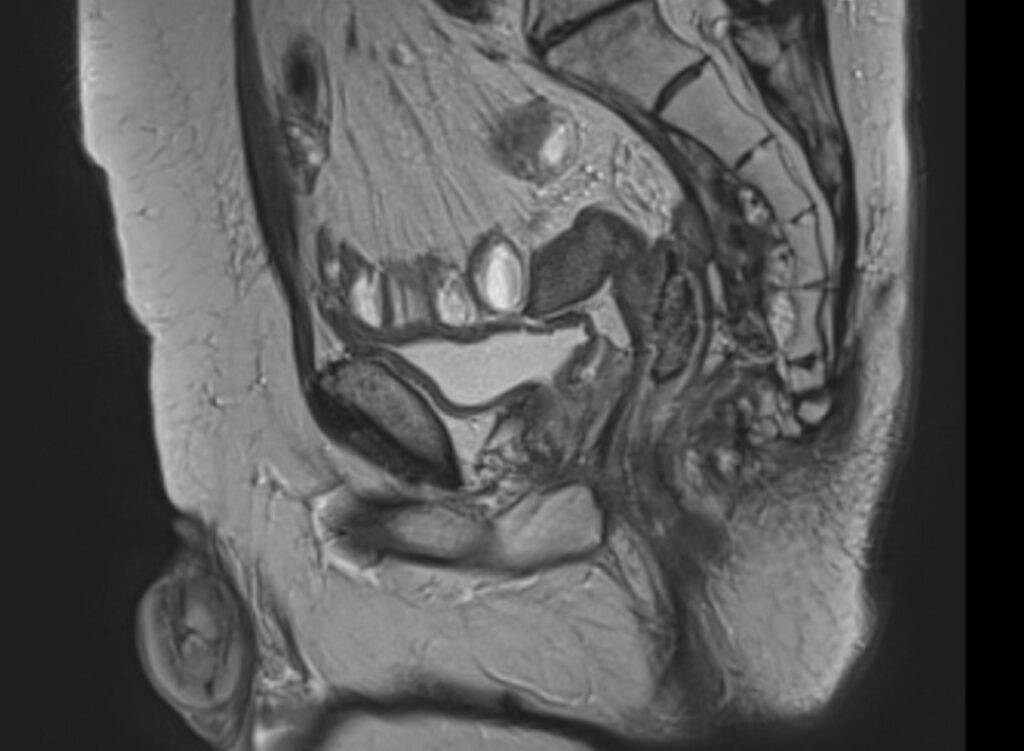

Über Magnetfelder wird ohne Strahlenbelastung das Körperinnere mit einem exzellenten Weichteilkontrast in hoher Auflösung dargestellt und ermöglicht eine präzise Beurteilung der Gewebeveränderungen.

Die MRT der Prostata erfolgt „multiparametrisch“ mit standardisierten Protokollen.

Mittels eines Bewertungssystems (PI-RADS-Score) werden die MRT-Bilder der Prostata ausgewertet und klassifiziert, als eine standardisierte Interpretation zur detaillierten Einschätzung des Prostatakrebsrisikos.

Die Prostata wird mit hochaufgelösten MRT-Bildern in allen Ebenen und mehreren Ansichten dargestellt sowie mittels verschiedener Funktionsmessungen analysiert.

Zunächst liegt der Fokus darin, in der Struktur und Signalgebung verändertes Drüsengewebe von gesundem Gewebe abzugrenzen. Als nächstes gilt es, verändertes Gewebe mit Funktionsmessungen (wie z.B. Zelldichte und Durchblutung) zu charakterisieren. Die diffusionsgewichtete MRT-Sequenz macht sichtbar, ob in verändertem Gewebe eine erhöhte Zelldichte – wie bei einem Prostatakarzinom – vorliegt. Die dynamische kontrastmittelangehobene MRT-Sequenz lässt Prostatakrebsareale mit einer erhöhten Durchblutung abgrenzen.

Als eine nicht-invasive Methode ist die MRT der Prostata eine schonende und völlig schmerzfreie Untersuchung, die frühzeitig eine Unterscheidung zwischen bösartigen, entzündlichen oder leichten Prostataveränderungen ermöglicht. Unabhängig der Prostatagröße ist die gesamte Prostata präzise beurteilbar und gewährleistet sogleich ein „Staging“ möglicher Prostatakrebsherde bezüglich Lage, Größe, Charakteristika und Ausbreitungsgrad.

Die multiparametrische MRT ist hierbei bildgebend die genaueste Methode im Nachweis von therapiebedürftigem Prostatakrebs, dass bei frühzeitiger Diagnose gute Heilungschancen hat. Sie liefert entscheidende Hinweise zur sodann ggf. gezielten Punktion der Prostata und Behandlung der Erkrankung.